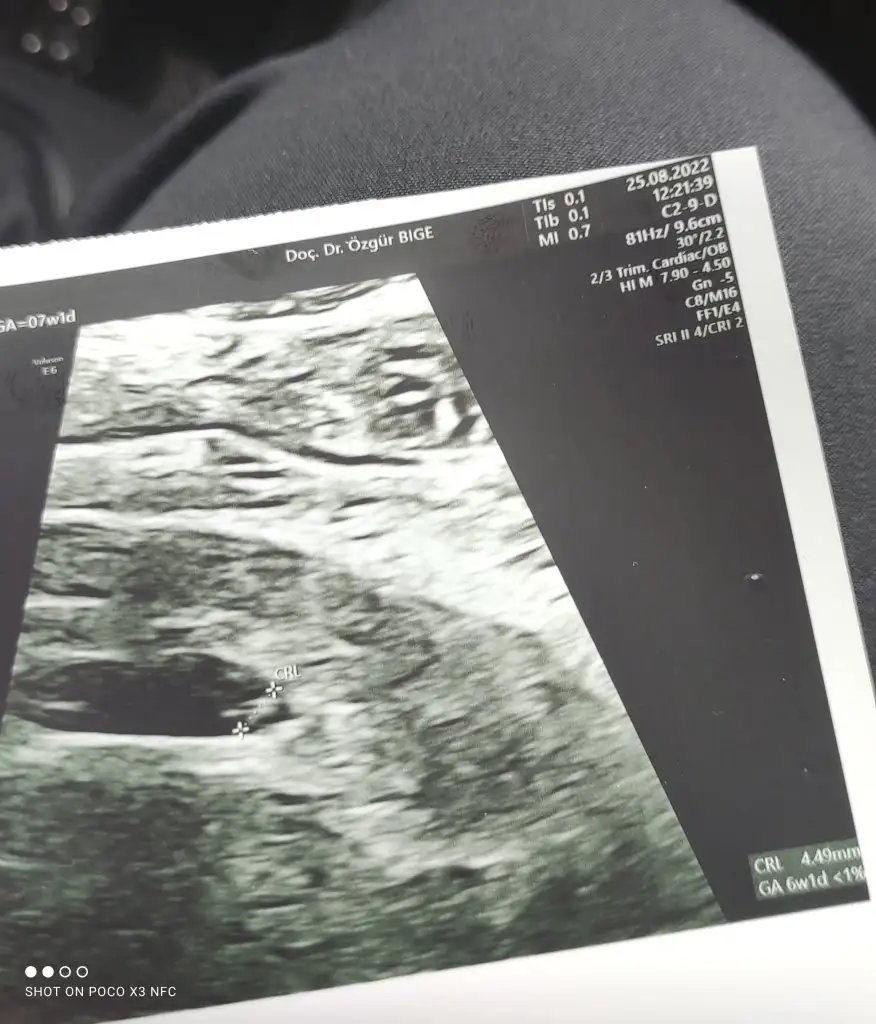

Bebeğin 0.64 cmEki Görüntüle 3118881

Anladım çok teşekkür ederimBebeğin 0.64 cm

6+3 gün ile uyumlu canım

At canım bakalımKızlar hastaneden geldim bebeğimin kalp atışını duydumdoktor gayet sağlıklı 1 ay sonra tekrar gel dedi hiç bir şey söylemedi başka. Siz ultrason fotoğrafından anlar mısınız?

0.27 cm 5+6 ile uyumlu mu peki canım yoksa çok küçük müBebeğin 0.64 cm